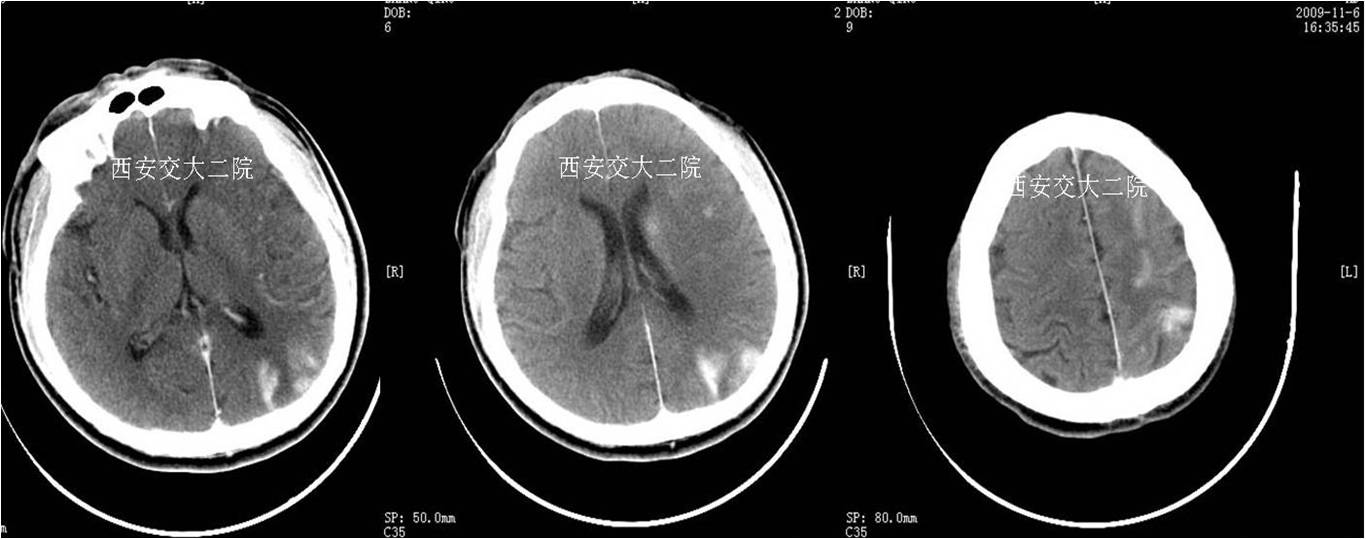

术后即刻CT

术后5天脑CT